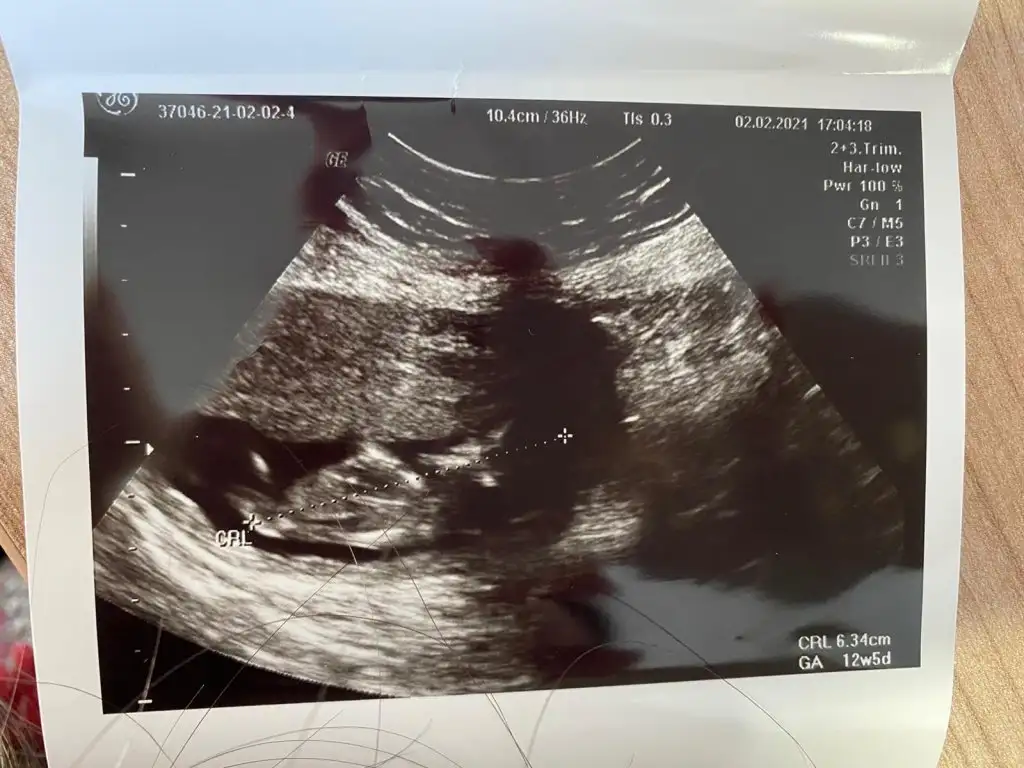

11+2 de ki karından ultrason görüntümüz bir şeyler gören varsa yazabilir mi? 😊

• WhatsApp Image 2021-02-03 at 11.18.20.webp

WhatsApp Image 2021-02-03 at 11.18.20.webp

32,8 KB · Görüntüleme: 206

• WhatsApp Image 2021-02-03 at 11.18.19.webp

WhatsApp Image 2021-02-03 at 11.18.19.webp

48 KB · Görüntüleme: 226

• WhatsApp Image 2021-02-03 at 11.18.18.webp

WhatsApp Image 2021-02-03 at 11.18.18.webp

39,5 KB · Görüntüleme: 202